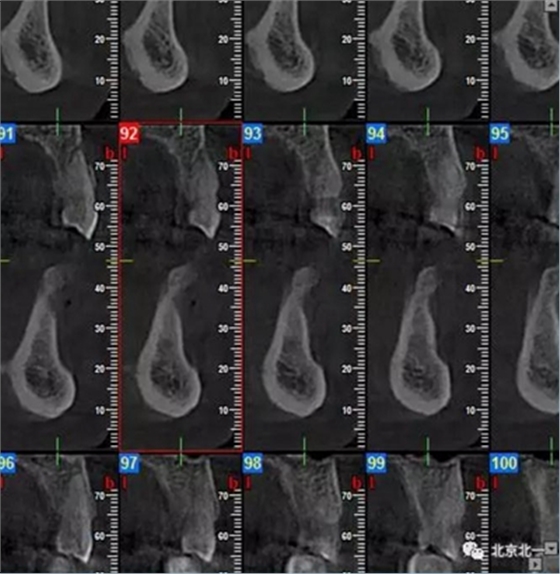

CBCT顯示如下圖